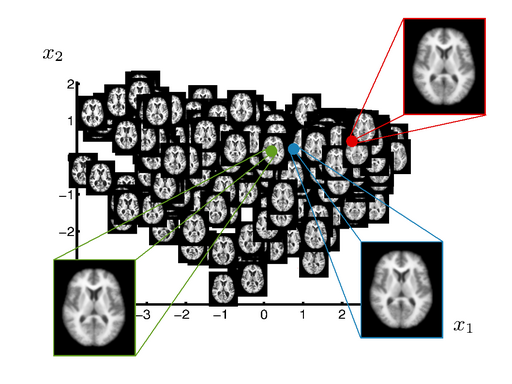

Manifold learned from OASIS database.